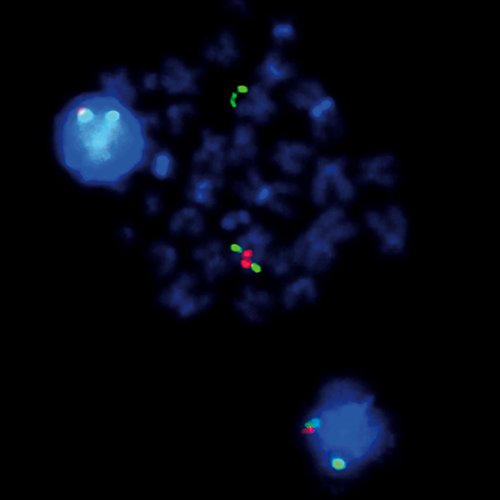

5q- (5q31; 5q33) probe hybridized to patient material showing a 5q33 deletion (1R2G).

The presence of del(5q), either as the sole karyotypic abnormality or as part of a more complex karyotype, has distinct clinical implications for myelodysplastic syndromes (MDS) and acute myeloid leukemia. Interstitial 5q deletions are the most frequent chromosomal abnormalities in MDS and are present in 10% to 15% of MDS patients. Two different critical regions are described, one at 5q31-q33 containing the CSF1R and RPS14 gene regions, characteristic for the '5q-' syndrome, and a more proximal located region at 5q13-q31 containing the CDC25C and EGR1 gene regions. The 5q- specific FISH probe is optimized to detect copy numbers at the CDC25C/EGR1 gene region at 5q31 and the CSF1R/RPS14 gene region at 5q33 simultaneously in a dual-color assay.